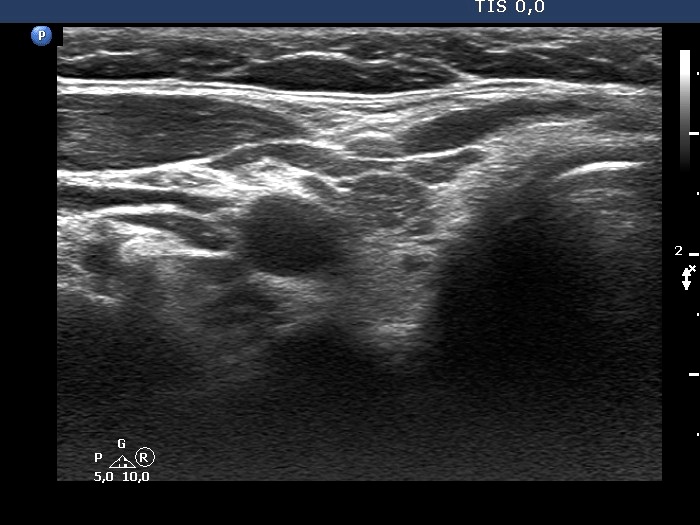

Ultrasonography. The thyroid was echonormal. There was a small hypoechogenic lesion in the right lobe while a nodular area in the left lobe. The latter had an upper, solid part and a lower, cystic part. The former presented echogenic granules and lines.Aspiration cytology was performed from the solid part and resulted in benign lesion.

Ultrasonography. The presentation remained unchanged. Using a better ultrasound device, it turned out that the echogenic granules are related to ventral cystic areas. Therefore, these are not microcalcifications, but figures caused by back wall cystic enhancement.Suggestion: yearly TSH determination, ultrasound in 4 years.

- The interpretation of the discrete lesions in the left lobe is difficult. I mean that this is a dominantly solitary nodule with a peripheral-type cystic portion. (See the explanation at the images.)